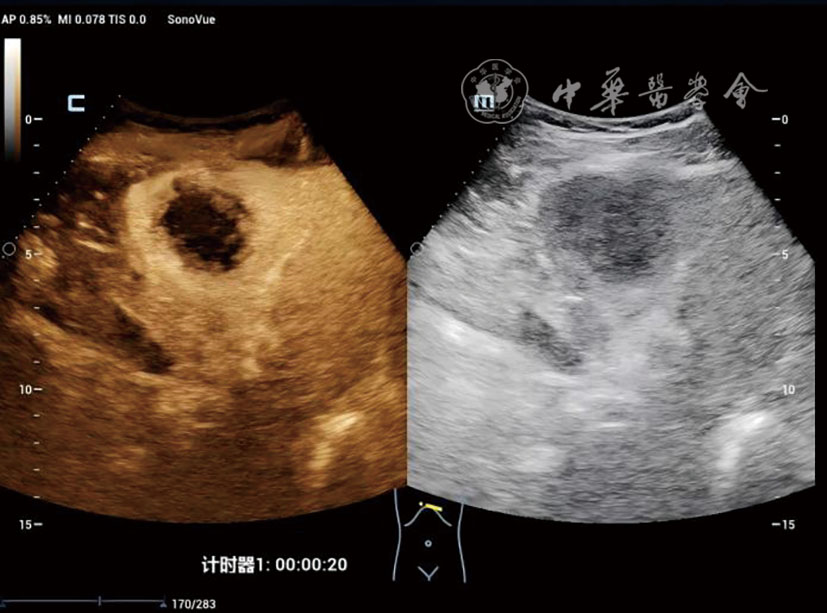

DPHCC组血清甲胎蛋白≥400 ng/ml的比例(48.4% vs 15.0%,P=0.002)及微血管浸润率(77.4% vs 17.5%,P<0.001)显著高于THCC组。超声造影显示,与THCC组相比,DPHCC组动脉期以不均匀增强(38.7% vs 15.0%)和环状增强(16.1% vs 2.5%)为主(P=0.003),且廓清时间更早[(91.94±37.58) s vs (131.65±59.71)s,P=0.002)]。多因素Logistic回归分析显示,肿瘤大小(OR=1.019,P=0.002)、甲胎蛋白≥400 ng/ml(OR=2.798,P=0.032)、边界不清(OR=3.204,P=0.020)及廓清时间<120 s(OR=2.221,P=0.049)是DPHCC的独立危险因素。

The DPHCC group showed significantly higher rates of serum alpha-fetoprotein (AFP) ≥400 ng/ml (48.4% vs 15.0%, P=0.002) and microvascular invasion (77.4% vs 17.5%, P<0.001) compared to THCC. On CEUS, DPHCC predominantly exhibited heterogeneous enhancement (38.7% vs 15.0%) and rim-like enhancement (16.1% vs 2.5%) in the arterial phase (P=0.003), with earlier contrast agent washout initiation (91.94±37.58 s vs 131.65±59.71 s, P=0.002). Multivariate analysis identified tumor size (odds ratio [OR]=1.019, P=0.002), AFP≥400 ng/ml (OR=2.798, P=0.032), ill-defined margin (OR=3.204, P=0.020), and washout time <120 s (OR=2.221, P=0.049) as independent risk factors for DPHCC.

表2 DPHCC组与THCC组患者的灰阶超声及超声造影特征比较[例(%)] |

廓清时间(s,![]() | 91.94±37.58 | 131.65±59.71 | t=3.41 | 0.002 |

| 动脉期增强方式 | - | 0.003 | ||

| 均匀增强 | 14(45.2) | 33(82.5) | ||

| 不均匀增强 | 12(38.7) | 6(15.0) | ||

| 环状增强 | 5(16.1) | 1(2.5) | ||

| 门脉期增强程度 | - | 0.060 | ||

| 高增强 | 1(3.2) | 4(10.0) | ||

| 等增强 | 4(12.9) | 13(32.5) | ||

| 低增强 | 26(83.9) | 23(57.5) | ||

| 实质期增强程度 | - | 0.157 | ||

| 高增强 | 1(3.2) | 0(0) | ||

| 等增强 | 0(0) | 3(7.5) | ||

| 低增强 | 30(96.8) | 37(92.5) | ||

| 内部灌注缺损 | χ2=0.13 | 0.722 | ||

| 无 | 27(87.1) | 36(90.0) | ||

| 有 | 4(12.9) | 4(10.0) |

注:DPHCC为双表型肝细胞癌;THCC为经典型肝细胞癌;-表示Fisher检验无统计值 |

表4 DPHCC的多因素Logistic回归分析结果 |

| 变量 | 参照组 | 比较组 | β值 | 标准误差 | Wald值 | P值 | OR值(95%CI) |

|---|---|---|---|---|---|---|---|

| 年龄 | - | - | 0.103 | 0.060 | 3.012 | 0.083 | 0.899(0.801,1.011) |

| 病灶最大径 | - | - | 0.019 | 0.006 | 9.210 | 0.002 | 1.019(1.007,1.032) |

| AFP | <400 ng/ml | ≥400 ng/ml | -1.704 | 0.687 | 6.148 | 0.032 | 2.798(1.103,7.147) |

| 内部回声 | 非低回声 | 低回声 | 0.741 | 0.432 | 2.941 | 0.087 | 2.099(0.901,4.898) |

| 边界 | 清晰 | 不清晰 | 1.964 | 1.512 | 1.688 | 0.020 | 3.204(1.195,8.503) |

| 动脉期强化 | 均匀 | 不均匀 | 0.585 | 0.410 | 2.038 | 0.150 | 1.796(0.799,3.998) |

| 廓清时间 | ≥120 s | <120 s | 0.798 | 0.406 | 3.863 | 0.049 | 2.221(1.002,4.923) |

| MVI | 阴性 | 阳性 | 3.968 | 1.042 | 14.503 | <0.001 | 0.019(0.002,0.146) |

注:DPHCC为双表型肝细胞癌;AFP为甲胎蛋白;MVI为微血管侵犯;-为连续性变量未赋值 |